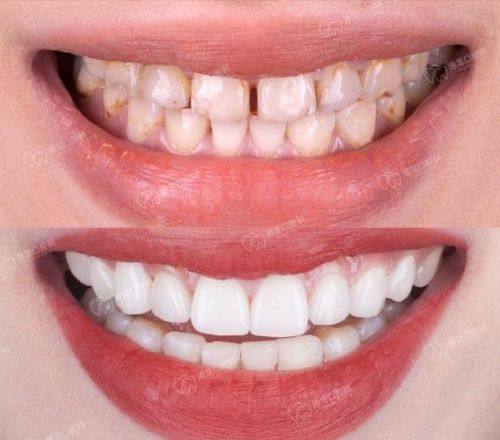

9. 牙齿美白:1000 - 3000元

5. 我想要牙齿美白,在同泽口腔做了牙齿美白项目。医生根据我的牙齿情况调整美白方案,成效特别明显。整个过程没有不适感,术后牙齿变得特别洁白,我非常满意这次的治疗成效。同泽口腔的技术和服务都值得称赞。